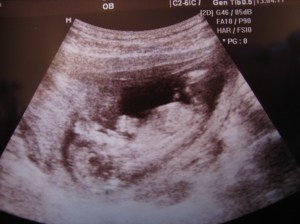

Da har vi vært på ultralyd, og det var fantastisk!!! Jeg var nervøs for at babyen ikke skulle ha det bra, men alt er normalt! Den lille tigeren har nå blitt større enn på 9 ukers ultralyden, og er nå 6,7 cm lang, hjertet slår 162 slag i minuttet, nakkefold og ryggrad er perfekt, og alt ser normalt ut 😀 Jeg og min kjære smilte stort, og jeg fikk en liten tåre i øyekroken.

Lillegull er veldig aktiv, og mens vi så på hikket den, suttet på tommelen sin, sparket med beina og vinket med hendene. Lillegull var også veldig ivrig etter å ta på hodet sitt, passet på å vise seg frem så vi fikk se han/henne skikkelig 🙂 Nå som jeg vet alt er bra kan jeg slappe av, og nyte å ha startet på andre trimester 🙂